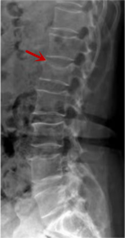

利器一:X線/DR

腰椎X線片作為最基礎(chǔ)的影像檢查手段,利于X線穿透人體組織后成像,以其快捷、直觀、價(jià)格低廉的特點(diǎn),X線檢查主要包括腰椎正側(cè)位、雙斜位以及過(guò)伸過(guò)屈位。主要用于觀察腰椎骨骼的情況,如椎體是否有骨折、骨質(zhì)增生程度、生理曲度的變化、椎體移位的情況等。然而,X線檢查也有它的局限性,無(wú)法判斷是骨折的新舊,對(duì)于椎體內(nèi)部結(jié)構(gòu)和周?chē)∪忭g帶組織(如脊髓神經(jīng)、椎間盤(pán)、韌帶等)的顯示不佳,另外X線作為有輻射檢查,孕婦及嬰幼兒謹(jǐn)慎選擇。

箭頭提示腰1椎骨折

箭頭提示腰3椎體滑脫